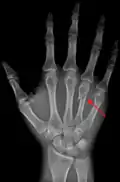

![]() Fourth metacarpal of the left hand (shown in red). Palmar view. | |

The fourth metacarpal bone (metacarpal bone of the ring finger) is shorter and smaller than the third.

The base is small and quadrilateral; its superior surface presents two facets, a large one medially for articulation with the hamate, and a small one laterally for the capitate.

On the radial side are two oval facets, for articulation with the third metacarpal; and on the ulnar side a single concave facet, for the fifth metacarpal.